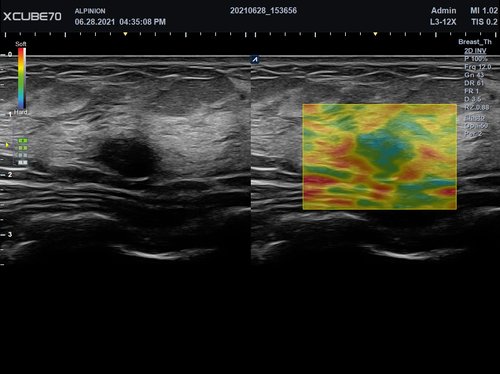

Das X-CUBE 70 bietet modernste Technologien für eine objektive und akkurate Diagnose. Intelligente klinische Module heben das System auf ein neues diagnostisches Niveau. Es erweitert Ihre Fähigkeiten und die Bandbreite Ihrer Möglichkeiten. Dazu gehören Module wie MicroView, point Shear Wave Elastographie (pSWE), oder auch die Kontrastmittelsonographie.

• L3-12X (3-12 MHz) für Ultraschalluntersuchungen in Bereichen MSK, Vaskulär, Weichteile, Pädiatrie, EM

• L3-8H (3-8 MHz) für Ultraschalluntersuchungen in Bereichen Brust, EM, MSK, Vaskulär, Weichteile